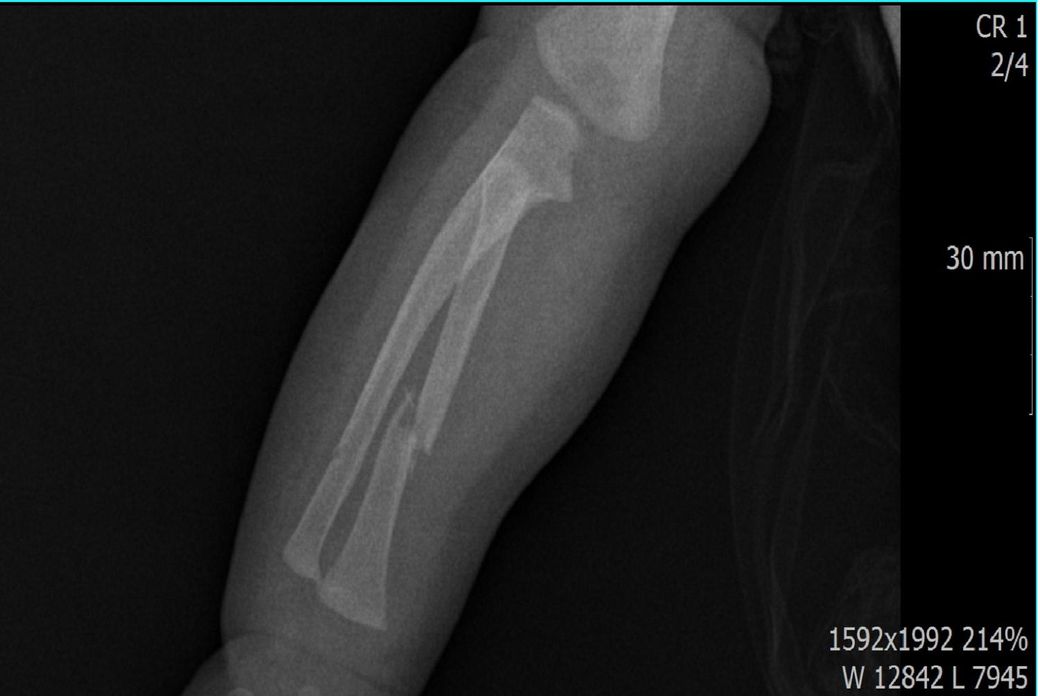

다름이 아니라, 첨부드린 엑스레이(X-ray) 사진처럼 골절 사실을 알게 되고 골절 발생 시점 대략적으로나마 추정시기를 파악하려고 문의 드리게 되었습니다

1) 3월 30일 촬영한 X-ray만으로 정확한 골절 시기를 100% 특정하는 데에는 한계가 있다는 점 충분히 인지하고 있기에 촬영날짜 기준으로 대략적으로 어느정도 시점에서 발생되었을 것으로 추측(ex 당일, 7~10일전, 7~14일 전, 10일 ~ 20일전, 14일 ~ 30일전 등등등)되는지 이해하고 싶습니다.

하지만, 아예 불가능한건 아니고 골절선이 얼마나 뚜렷하냐, 골막 반응이 보이느냐, 연골성 가골 형성이 있느냐 등으로 골절 시기를 추정해볼 수 있습니다.

골절선이 뚜렷하면 0~1주, 골막 반응이 시작되면 1~2주, 연골성 가골이 형성되기 시작하면 2~3주, 가골이 명확해지면 3~6주 정도로 추정할 수 있습니다.

골절선이 흐려졌고 가골이 형성되기 시작하는 2~3주경이 아닌가 의심이 되지만 제가 골절을 주로 보는 정형외과 전문의가 아니라서 정확도가 떨어집니다.

영상의학과 전문의나 정형외과 전문의의 고견을 구해보시는게 도움이 되겠습니다.